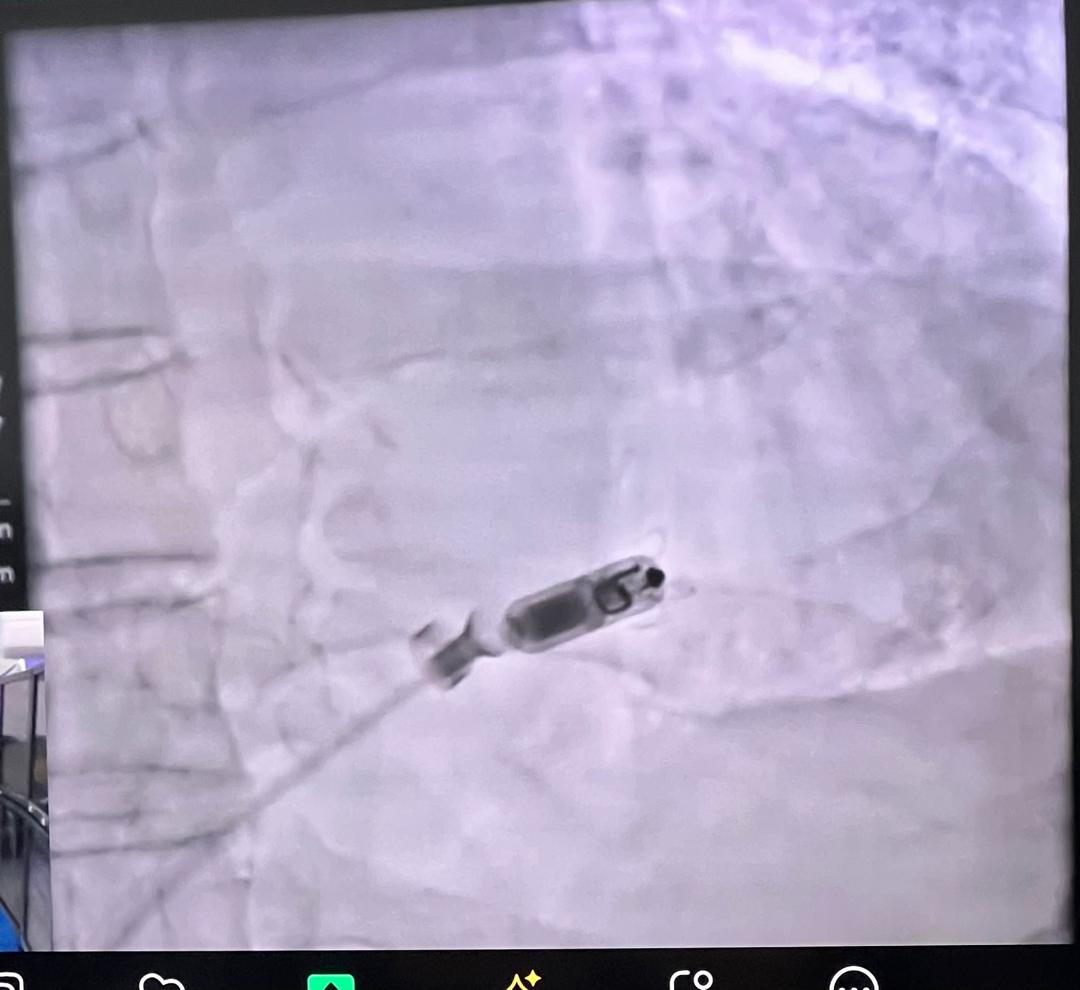

Thrilled to share that the EMBOL-AF Registry (>450 embolic complications of AF ablation) has been accepted for a LBCT session at EHRA 2025!